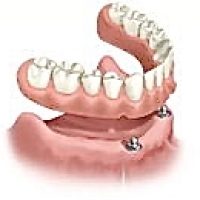

Denne løsning fungerer ved, at der indsættes implantater i kæben, der fungerer som en tryklås. På protesens bund sidder der en trykknap, som ´knappes´ fast på implantatet. Det sikrer, at protesen sidder helt fast i munden, selvom du ikke har egne tænder at sætte den fast på. Drejer det sig om en protese i overmunden, er der desuden den fordel, at din udtale bevares samt følelsen af at smagsoplevelsen bliver bedre , da protesen så kan blive ganefri.

Hvis det vurderes, at det er muligt i dit tilfælde, er det også muligt at lave en tryklåsbro i stedet for en fastskruet bro. Fordelene ved denne løsning er, at den først og fremmest ikke fylder mere i munden, end dine egne tænder gjorde. Samtidig har du mulighed for at holde en bedre mundhygiejne, da tryklåsprotesen kan tages ud af munden og rengøres.